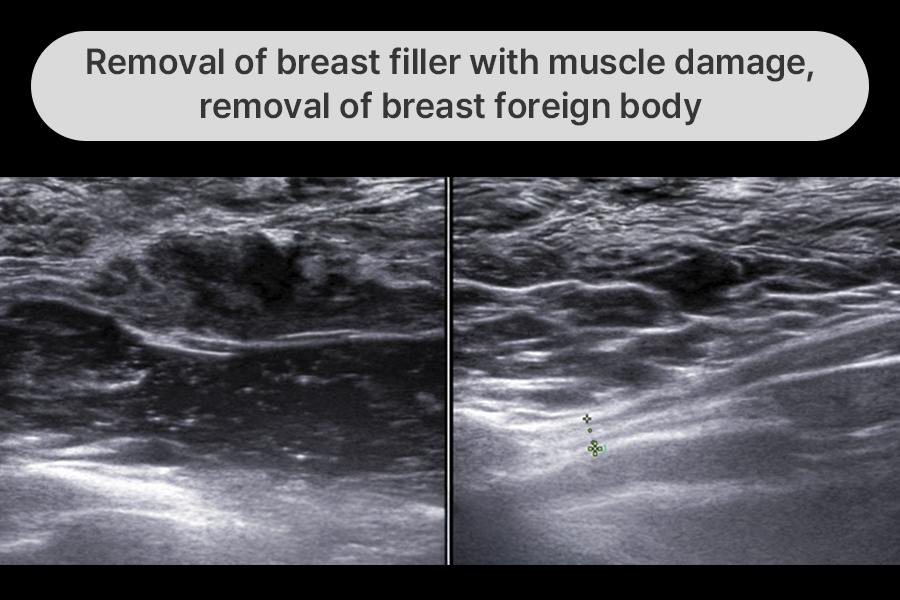

Patient with bloody nipple discharge

due to muscle damage after filler injection

PAAG, the main target of surgical filler removal, is toxic in the body.

Especially when muscle tissue damage occurs, it shows various symptoms ranging from

mild filler migration to severe inflammation, hematoma, and muscle tissue rupture.

This patient came worried about breast cancer due to bloody nipple discharge.

We removed the breast filler along with damaged tissue, hematoma, and torn muscle tissue.